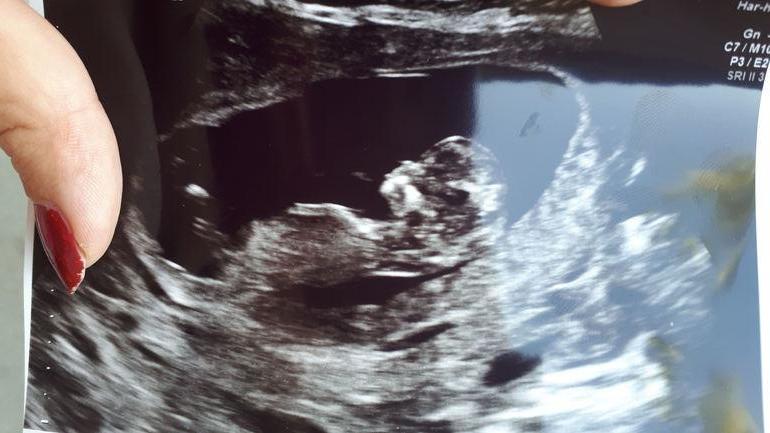

Мальчик или девочка.

Угол больше к девочке стремится. Но и наклон все-таки есть как шанс на мальчика. Это именно по этому фото:) у меня девочка прям 1000% был бугорок ровно параллельно спинке:) у вас есть над чем посомневаться на фото:)

Почему все пишут что нельзя определить 🤷🏻‍♀️ Можно же по наклону полового бугорка! Если снимок удачный и его видно! У вас я повнимательнее посмотрела и думаю девочка у вас, я не туда сначала глянула))) .. просто фото такое не четкое.. у меня было видно что дочка! Бугорок был параллельно спинке.. конечно я все равно сомневалась но как вышло зря! Так что не надо так уверенно говорить что определить нельзя! Может не 100 процентов но на 70-80 предположить точно можно

На Узи сказала скорее всего девочка. Но рано говорить

Могу по своему опыту 100% сказать что это ребёнок)) А вот кто именно скоро узнаете) сейчас еще рано, да и по этому фото не сказать, ведь ребёночек боком)

Либо не видно бугорок либо мальчик, больше нет фото?

В 11 недель пол не определяют.

Мне по узи ставили 12 недель и 4 дня по моим подсчетам 11 недель

Ещё как определяют , мне один профессор сказал , плюньте тому узисту в лицо кто вам пол не скажет на 11 неделе и бегите от него, потому что это самое простое что можно определить сразу , и такой узист вряд ли сможет органы рассмотреть .

Сынок Определение пола по бугорку)